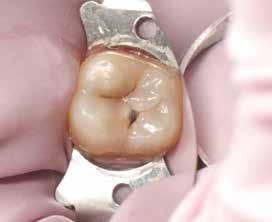

3. ábra: A preparálás, a bondozás és a kompozit felvitele után. (Megjegyzés: némi kompozit túlfolyás látható a mesiális doboz axiális falain).

4. ábra: A durva finírozás után a restauráció pereme sima és anatómiailag is megfelelő.